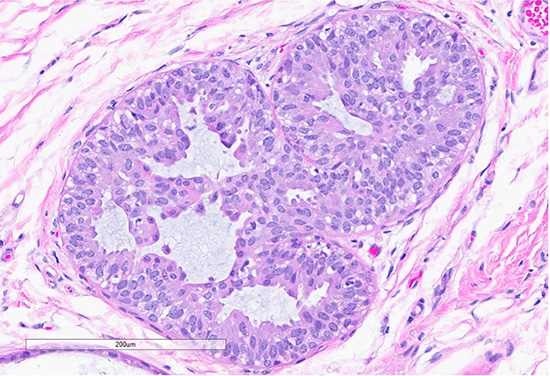

Figure 1: Microscopic slides of collagenous/mucinous spherulosis. Low-power (10× objective) H&E-stained section (top) shows cribriform architecture with collagenous/mucinous spherulosis. High-power (40× objective) H&E-stained section (bottom) demonstrates further detail, with myoepithelial cells surrounding round collagenous/mucinous spherules filled with intraluminal acellular basement membrane material.

Collagenous spherulosis (CS) is a rare, benign intraductal proliferative lesion of the breast1. It arises from the proliferation of basement membrane material, forming luminal hyaline spherules (eosinophilic to basophilic, occasionally mucoid, like this current case), surrounded by myoepithelial cells. These spherules contain a mixture of basement membrane components, banded collagen, and mineral deposits1.